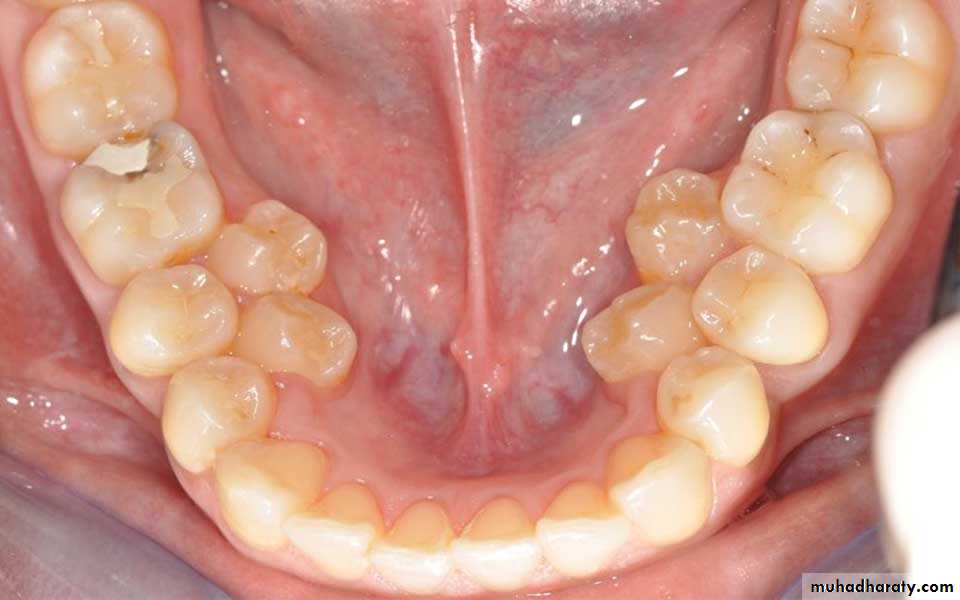

2. HYPERDONTIA

Teeth appear in addition to the regular number of teeth (supernumerary teeth). Extra primary teeth are more common. Proliferation of permanent or primary dental lamina to form many tooth germs (during initiation). Supernumerary teeth can be classified by shape and by position. The shapes include:

• Supplemental (the tooth has a normal shape for the adjacent teeth)

• Tuberculate (the tooth has tube or barrel shaped);• Conical (The tooth is wide at the base and narrows near the top ,”peg shaped");

• Compound odontome (multiple small tooth-like forms);• Complex odontome (a disorganized mass of dental tissue)

Locations of extra teeth include:Paramolar. An extra tooth grows in the back of your mouth, next to one of your molars.

Distomolar. An extra tooth grows in line with your other molars, rather than around them.

Mesiodens. An extra tooth grows behind or around your incisors.